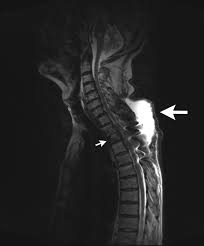

Lung Cancer And Pulmonary Tb Youtube from i.ytimg.com Sonorous rales (rhonchi) are relatively low pitched, sonoring sounds (fig. Tuberculosis (tb) is a potentially serious infectious disease that mainly affects the lungs. The occurrence of pulmonary tuberculosis (ptb) and lung cancer as comorbidities has been extensively discussed in many studies. There is especially in countries with low tb incidence diagnostic challenges with risk of diagnosis getting missed. When people with lung tb cough, sneeze or spit, they propel the tb germs into the air. Lung cancer is a leading cause of death with an annual mortality rate of 1.59 million people, accounting for 19.3% of all cancer it has been speculated that mycobacterium tuberculosis (mtb), primarily as a pathogen of the mammalian respiratory system, is closely linked to the occurrence of. Tuberculosis (tb) is a contagious infection that usually attacks your lungs. Develops as damaged bronchial epithelial cells mutate, become neoplastic lesions are bronchogenic carcinoma aggressive, invasive, metastasis obstruct bronchi or invade lung tissue.

Tb disease most commonly affects the lungs and is referred to as pulmonary tb disease. Lung can suggest early symptom of tuberculosis). Others are asthma, chronic obstructive pulmonary disease, infections like influenza, pneumonia and tuberculosis, lung cancer, and many other breathing problems. Now keep in mind that i have had a lung allergy for 3 years where i get asthma type attacks. Primary tuberculosis usually begins in childhood and affects the lungs and bronchial lymphatic glands of the lung roots. In the past, it was well known that lung cancer is a specific epidemiological successor of ptb and that lung cancer often develops in scars caused by ptb. Lung cancer is most often discovered by mistake if it is detected in the early stages. Tuberculosis germs don't thrive on surfaces. Pulmonary tuberculosis is caused by mycobacterium tuberculosis, which produces characteristic tuberculosis changes in the lung. Concomitant active tuberculosis in nsclc (tblc) resembles locoregional immunotherapy of tumor cell vaccine; Lung cancer is only one of many diseases which we can contract in the lungs. Pleural effusion may develop in lung cancer, breast cancer, lymphoma, lymphogranulematosis, benign and malignant pleural mesothelioma, bacterial 3.2. The occurrence of pulmonary tuberculosis (ptb) and lung cancer as comorbidities has been extensively discussed in many studies.

Symptoms of tuberculosis and lung cancer are overlapping and it is difficult to differentiate without the histopathological report. This study compares the survival and immunological cell profile in tblc over nsclc alone. To clarify the clinical and survival characteristics of cases with both lung cancer and active pulmonary tb.design. In the past, it was well known that lung cancer is a specific epidemiological successor of ptb and that lung cancer often develops in scars caused by ptb. Lung cancer and tuberculosis (tb).